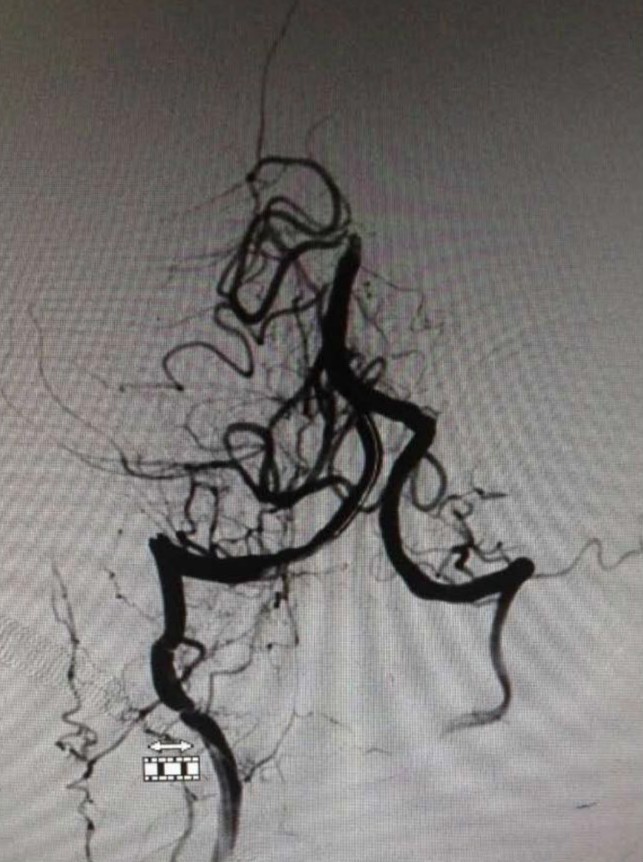

▼右椎动脉造影见基底动脉末端闭塞。双侧颈内动脉造影无殊,双侧后交通未见显影。